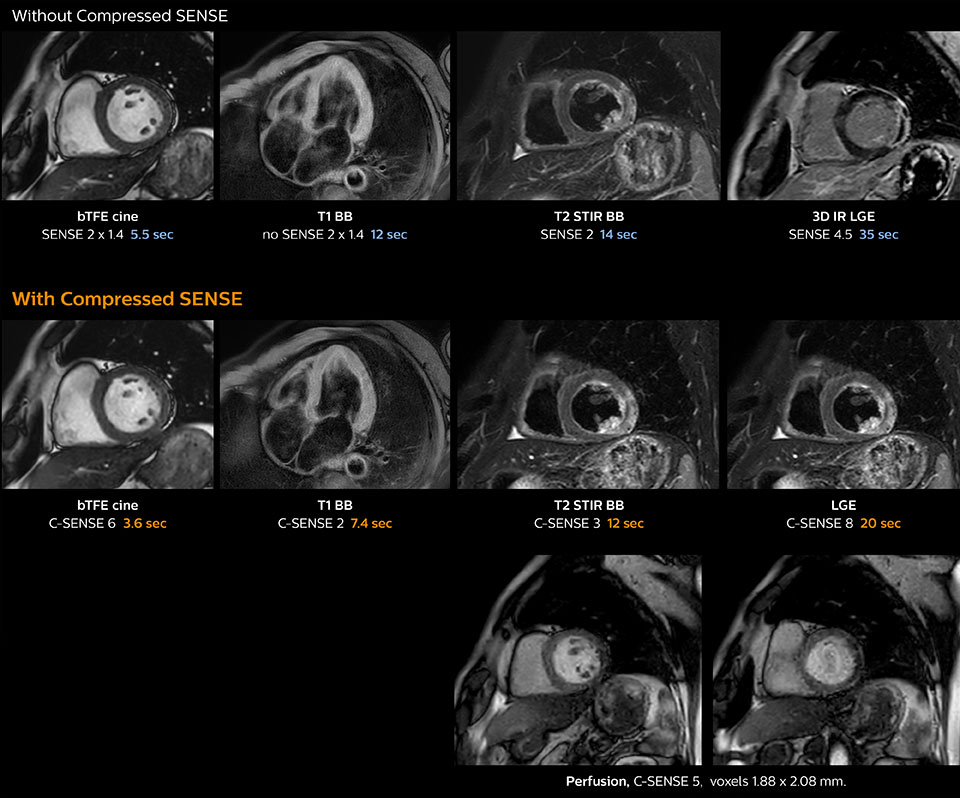

Cardiac MRI of acute myocardial infarction (AMI) w/wo Compressed SENSE

These images of a patient with acute myocardial infarction images were acquired on Ingenia 1.5T with and without Compressed SENSE.

Dr. Koshi Miyake, cardiologist, explains that scanning of patients with cardiac arrhythmia can be challenging, as scanning times can become very long due to the varying heart rate. So his most important motive to implement Compressed SENSE in cardiac MRI exams was to reduce the burden of breath holds for the patient, while maintaining high image quality. He hopes this can also help to reduce motion caused by the difficulty for patients to hold their breath.

“Compressed SENSE has now been implemented in all cardiac exams. Thanks to the acceleration, fewer breath holds are now needed, or breath hold times are shortened. This reduces the burden of the exam for cardiac patients, without affecting the quality of information required for cardiac function analyses,” he says. “Because it’s easier for patients to comply with the breath hold times”

“In our previous cardiac cine sequence, we were acquiring two slices during one breath hold. With Compressed SENSE, we increased this to four slices per breath hold. It is also possible to shorten scanning time using a C-SENSE factor 6 without sacrificing image quality.”

“Typically, in scans with high contrast, such as 2D balanced TFE cine, a quite high C-SENSE factor may be used. When we tried a higher C-SENSE factor, we saw still no significant influence on cardiac ejection fraction, but 2D image quality started to decline. For coronary imaging, we use a C-SENSE factor of 3 in 3D balanced TFE, or even up to 4 when contrast is high.”